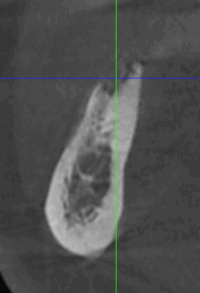

Lorsque l’os de la mâchoire est insuffisant pour soutenir un implant dentaire, des techniques de reconstruction osseuse peuvent être nécessaires. Ces procédures permettent d’augmenter le volume osseux pour garantir la stabilité de l’implant.

- Greffe osseuse : Ajout d’os ou de matériaux pour augmenter le volume osseux.

- Régénération Osseuse Guidée : Stimule la repousse osseuse grâce à des biomatériaux.

- Sinus Lift : Augmentation de l’os dans la région des molaires supérieures par élévation des sinus.